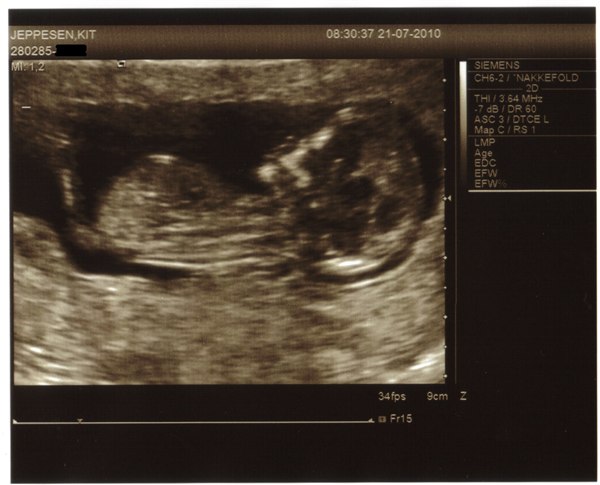

Så blev det endelig vores tur. Var til NF scanning i går.

Blev scannet af en super sød jordemoder, der var rigtig god til at fortælle alt hvad hun scannede/målte undervejs. Følte mig meget tryg og velinformeret. Blev scannet på Hillerød Hospital. Jeg blev rykket 1 dag, så termin er 30-1-2011.

Alt så godt ud og vi fik lav risiko for DS.

Vedhæftede fotos (klik for at se i fuld størrelse)